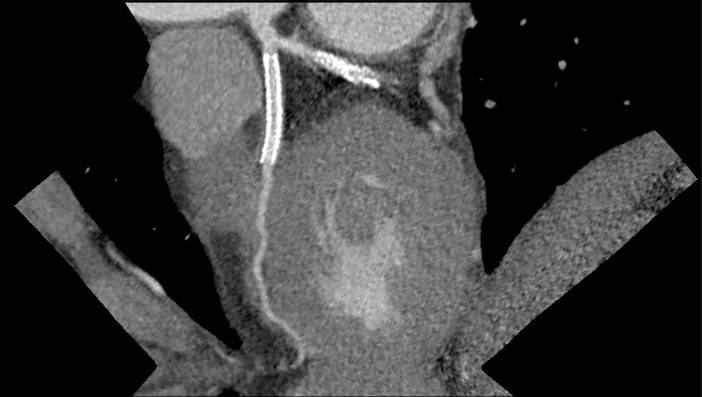

Case Study (70% LAD Block)

Case Study (70% LCX Block)

Case Study (Stent - LAD & LCX)

Case Study (Triple Vessel Block)